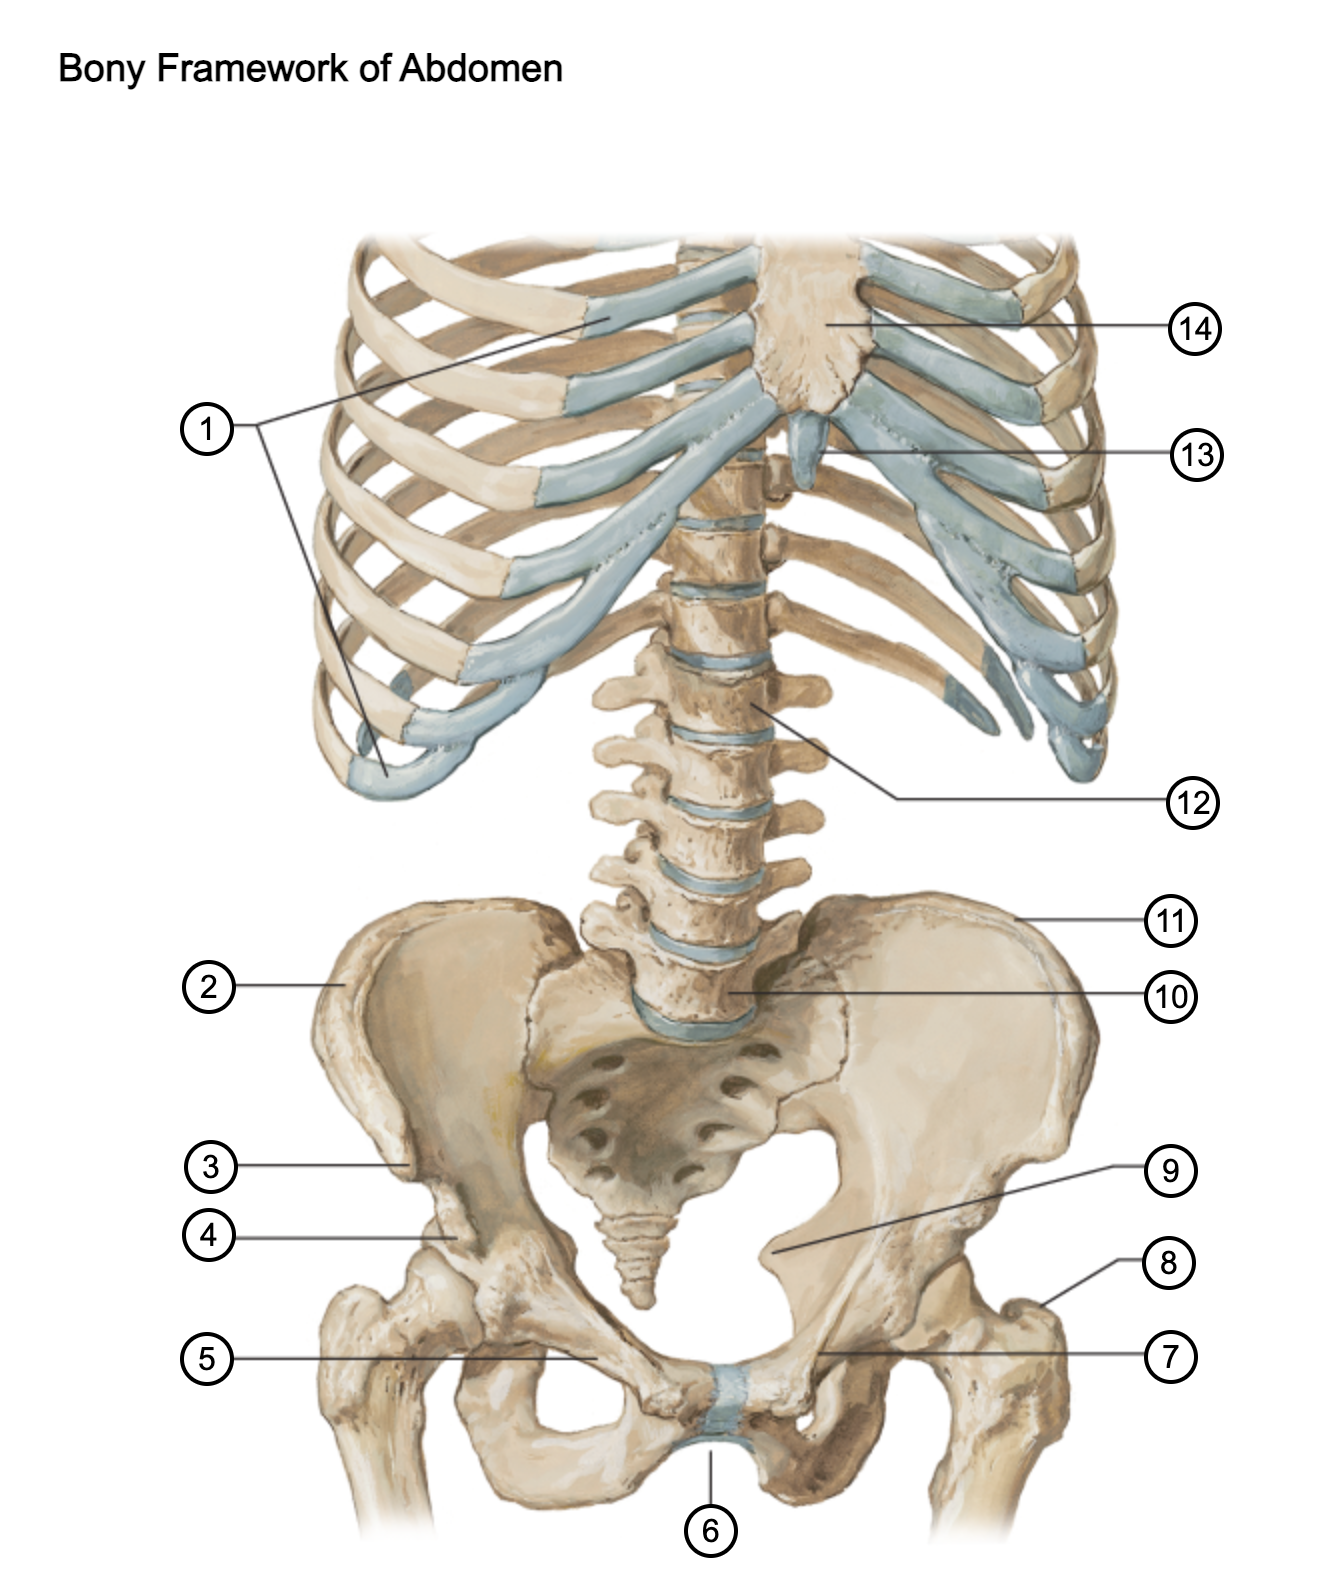

1

costal cartilages

2

iliac crest

3

anterior superior iliac spine

4

anterior inferior iliac spine

5

superior pubic ramus

6

pubic arch

7

pecten pubis

8

greater trochanter

9

ischial spine

10

L5 vertebra

11

iliac crest

12

L1 vertebra

13

xiphoid process

14

body of sternum